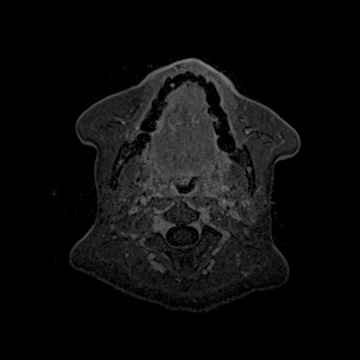

頚部腫瘍

- 造影3D VIBE

- 体動の影響を受けにくい